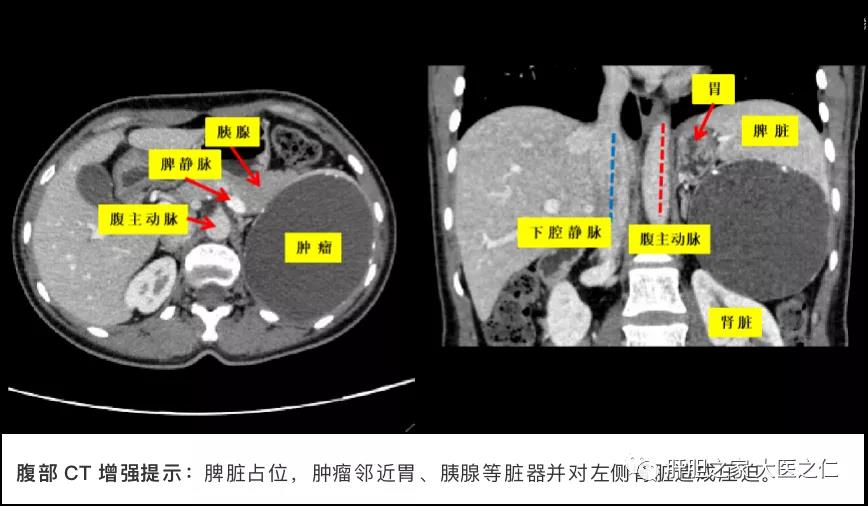

患者34岁,女性,因体检发现脾脏占位性病变半月余就诊于我院红角洲院区肝胆外科门诊,入院后完善相关检查,腹部CT提示脾脏囊性病灶并边缘多发钙化,肿瘤大小约为10.5cm×8.2cm×8.9cm。

将患者的CT数据导入三维可视化软件重建脾脏及其动静脉和周围脏器的三维立体模型,我们可以更清楚的观察到肿瘤与脾脏动脉、静脉和肾脏的关系,并通过脾脏动脉流域分析,确定脾脏切除的界面及需要保留的动脉血管支。王恺教授在仔细地观察CT及三维重建模型的基础上,凭借丰富的手术经验及高超的手术技术实现了突破。在术中充分游离脾周血管后离段近肿瘤区域的脾蒂,严格按照脾脏动脉血液供应范围,精准地切除肿瘤及靠近肿瘤的部分病变脾脏,保留正常部分脾脏及其供血的主要血管支,顺利完成了腹腔镜下脾脏部分切除。手术历时90分钟,术中出血200ml。术后在黄跃英护士长团队精心指导及护理下,患者术后恢复良好,在术后第4天拔除腹腔引流管,第7天顺利出院,体现了肝胆外科快速康复外科理念(ERAS)。